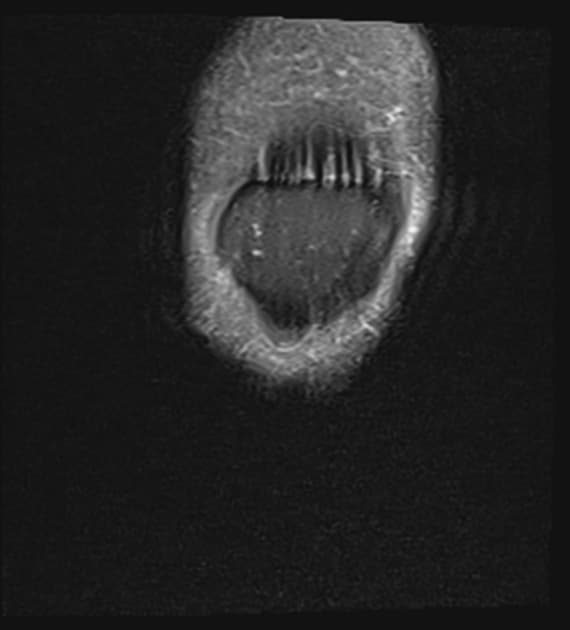

Coronal PD fat sat

MRI•Coronal PD fat sat•1 / 37

Ca bệnhXé dạng tay xô sụn chêm trong

Xé dạng tay xô sụn chêm trong

- Xé đa hướng sụn chêm trong với thành phần xé dạng tay xô lớn (multidirectional tear of the medial meniscus with a large bucket handle component).

Xé dạng tay xô sụn chêm trong trên bệnh nhân có tiền sử xé dây chằng chéo trước từ trước và đau dọc đường khớp trong. Ghi nhận mảnh sụn chêm dạng "tay xô" bị lật ngược vào trong rãnh gian lồi cầu (flipped 'bucket handle' meniscal flap within the intercondylar notch).

Xé dạng tay xô sụn chêm trong (Bucket handle tear medial meniscus)

- "Dấu hiệu 'sụn chêm bị lật' trong rãnh gian lồi cầu là phát hiện MRI quan trọng để chẩn đoán xé dạng tay xô."

Xé dạng tay xô sụn chêm trong là một vết rách dọc theo chiều dọc với mảnh rách nội vi bị di lệch vào rãnh gian lồi cầu, thường gây nhầm lẫn như một khối u. Tình trạng này thường xảy ra ở bệnh nhân trẻ sau chấn thương gối cấp tính, đặc biệt khi có rách dây chằng chéo trước. Mảnh sụn bị di lệch, gọi là 'tay xô', có thể gây hiện tượng khóa khớp, đau và hạn chế vận động. Chụp cộng hưởng từ (MRI) rất nhạy trong việc phát hiện tình trạng này, với các dấu hiệu hình ảnh điển hình như dấu hiệu 'PCL kép' và mất dấu hiệu 'nơm bắt bò'. Việc nội soi khớp đánh giá và điều trị sớm được khuyến cáo để ngăn ngừa tổn thương sụn và phục hồi chức năng gối.